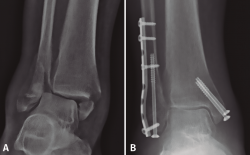

Clavo intramedular de peroné

Las ventajas descritas en el tornillo intramedular de peroné son aplicables al clavo intramedular de peroné. Varios estudios describen estas ventajas del uso del clavo intramedular de peroné en el paciente anciano, en cuanto a menor agresión de las partes blandas, mayor respeto de la biología ósea, menor prominencia de material y sobre todo menor tasa de complicaciones de partes blandas, como dehiscencias o infecciones, en comparación con la osteosíntesis convencional(12,18,54,57,58). Algunos autores llegan a considerarlo el tratamiento de elección en pacientes con problemas de partes blandas previos a la cirugía o con alto riesgo de complicaciones(57).

Jordan(12) realiza una revisión sistemática donde incluye 10 estudios con 711 fracturas inestables de tobillo tratadas con clavo intramedular de peroné y concluye que no hay diferencias en el resultado funcional final pero sí menores complicaciones que con la osteosíntesis convencional. Debe resaltarse que en 7 de los estudios incluidos en esta revisión autorizaban al menos la carga parcial y en 2 de ellos la carga completa dependiendo del patrón de fractura(12).

White(18) publica un ensayo clínico aleatorizado con 100 pacientes mayores de 65 años con fractura de tobillo inestable, comparando el clavo intramedular con la osteosíntesis convencional, autorizando la carga protegida según la tolerancia en ambos grupos. No encuentra diferencias significativas en el resultado funcional pero sí en las complicaciones de partes blandas (16% de infecciones en el grupo convencional versus 0% con el clavo). En ambos grupos presenta pacientes con necesidad de retirada de material (12% en el grupo convencional y 10% en el grupo del clavo, siendo en este último grupo solo la retirada de algún tornillo de bloqueo). El autor refiere que, aunque el coste del implante es mayor, el coste global fue inferior en el grupo del clavo al sumar el coste del tratamiento de las complicaciones. También señala la ventaja de no demorar la cirugía por inflamación y un tiempo quirúrgico menor en el grupo del clavo(18).

Una de las principales limitaciones que tenían estos clavos en sus primeros diseños eran la migración del implante y el acortamiento del peroné; sin embargo, con los nuevos implantes con bloqueos proximales y distales, estos problemas han disminuido y nos han permitido ampliar sus indicaciones, como en las fracturas conminutas, permitiendo mantener la longitud del peroné y evitando su acortamiento(54,57,58). Además, los nuevos clavos presentan la opción de estabilizar lesiones asociadas de la sindesmosis(18,58).

Estudios biomecánicos en cadáver han demostrado superioridad de los nuevos clavos en la resistencia a la torsión en comparación con la osteosíntesis convencional (placa tercio de caña y tornillo interfragmentario) en fracturas transindesmales con hueso osteoporótico(59). Sin embargo, en comparación con las nuevas placas bloqueadas, un estudio biomecánico demuestra que los clavos presentan menor resistencia a la torsión en fracturas simuladas de tipo Weber C conminutas, pero sin diferencias en la diastasis de la sindesmosis, y presentando similares características de fallo en ambos implantes(60).

Como consideración técnica, Bugler(58) en su serie presenta complicaciones de acortamiento y subluxación lateral en algunos casos iniciales sin bloqueo del clavo o solo el bloqueo distal. Recomienda el doble bloqueo con un tornillo proximal transindesmal (independientemente de si existe o no lesión de la sindesmosis) y un tornillo distal anteroposterior, para aumentar la estabilidad y mantener la longitud, no presentando las complicaciones previas con esta modificación técnica y con buenos resultados radiológicos y clínicos.